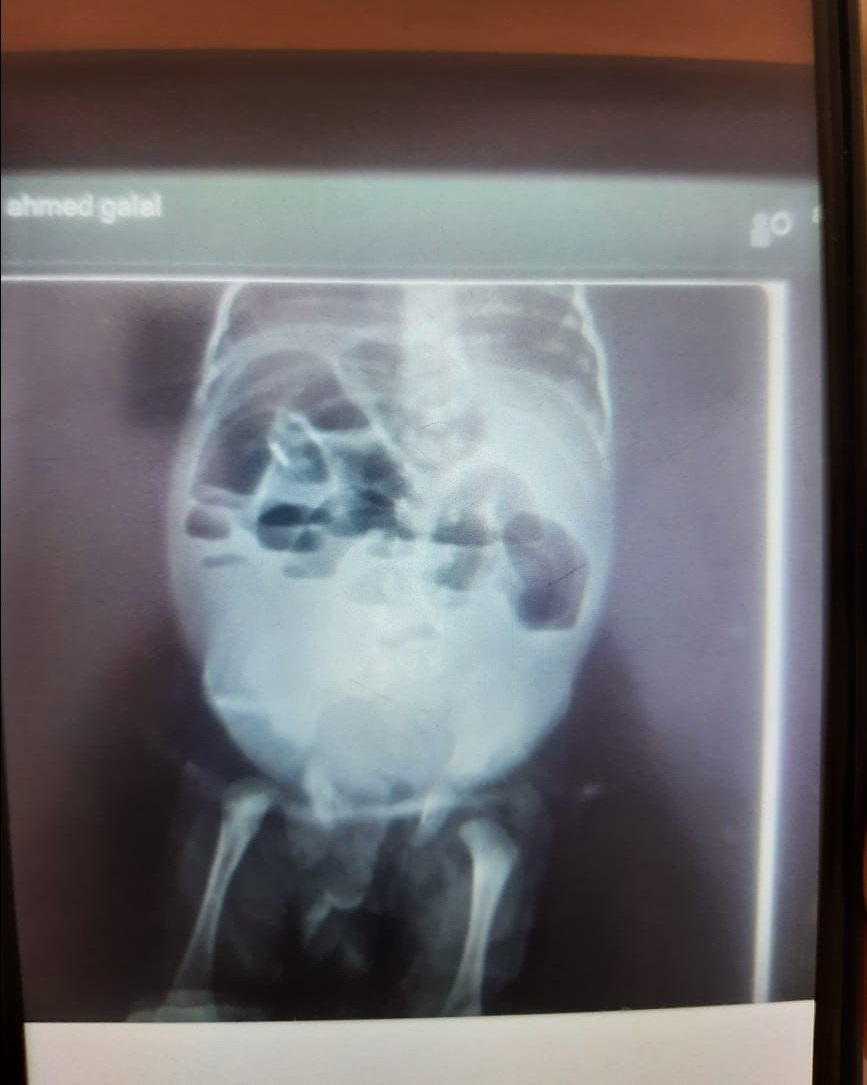

Plain X-ray abdomen standing showed severe gaseous distension, multiple sharp air fluid levels, and absence of gas distribution in the lower abdomen. The cardiac shadow was obscured (Figure 1).